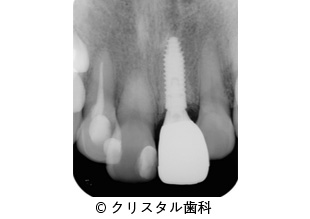

【症例1】破折した左上1番にインプラント治療した症例

- 破折した左上1番にインプラント治療した症例

- 523,500円(税込)

- 4ヵ月

患者様の症状

食事中に前歯が突然動き出し、診断の結果、歯の破損が原因であり、患者様よりインプラント治療を希望されました。

治療法

歯根破折を起こした左上1番の歯に代わって、インプラント(人工の歯根)を埋入する治療を行いました。

その後、インプラントにはセラミックスの歯を被せることで、審美的にも機能的にも回復した。 -

治療結果

インプラント治療によって歯根破折を起こした歯を補うことでき、審美面・機能面に患者様より満足のご感想をいただいた。

治療を行う上での 注意点 (リスク・副作用)

出血、疼痛、インプラント周囲炎。